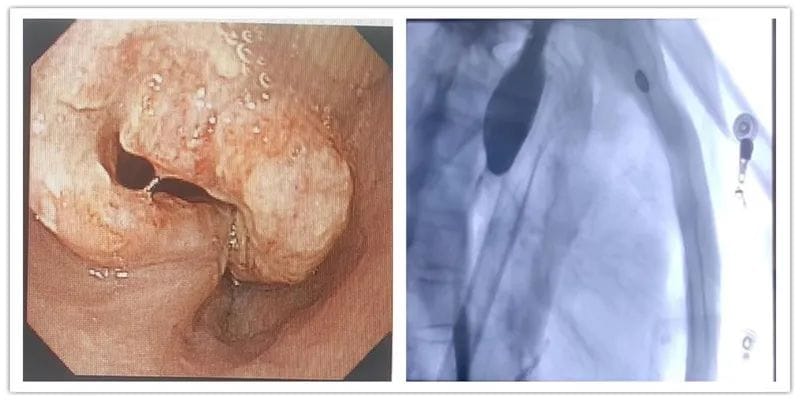

病例一:老年患者王某某,确诊食管癌3+月,外院化疗术后2月后就诊。该患从发现时食管腔已是重度狭窄,经化疗后,虽癌肿缩小,但因瘢痕形成,狭窄更甚,从最初的流质饮食,到如今的稀饭都无法下咽,患者异常痛苦,骨瘦如柴。入院完善相关检查后,在郭军主任的指导下,消化内科贺黔黔医生成功为其实施了内镜下食管癌支架置入术,术后患者无任何不适,第二天已可进流质饮食。此时正逢端午佳节,老人已能少量进食,对于一个长期不能进食的患者来说,手术的成功为提高患者后期生活质量意义非凡,后期消化内科将在临床营养科的指导下,继续给予患者营养支持治疗。

食管癌化疗前(左)及支架置入前(右)

支架置入后